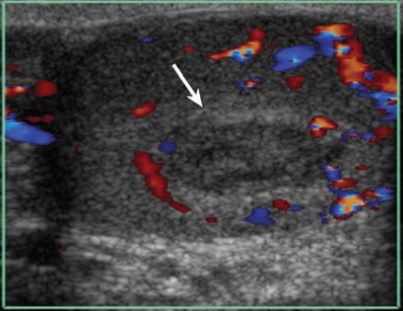

- Mất tưới máu trong tinh hoàn: vỡ tinh hoàn sẽ làm mất tưới máu một phần hay toàn bộ tinh hoàn tùy mức độ thương tổn (Hình6).. Đây là một dấu hiệu rất quan trọng giúp đánh giá khả năng sống của nhu mô tinh hoàn và quyết định phương pháp phẫu thuật. Mất tưới máu 1 vùng trong tinh hoàn có thể là thứ phát sau tụ máu trong tinh hoàn (Hình7).. Nếu vùng thiếu tưới máu lớn có thể phải phẫu thuật lấy khối máu tụ.

Hình 7.  Máu tụ trong tinh hoàn

* Nguồn: theo Bhatt S (2008) [2]

+ Mất tưới máu trên siêu âm Doppler màu nên chỉ định mổ